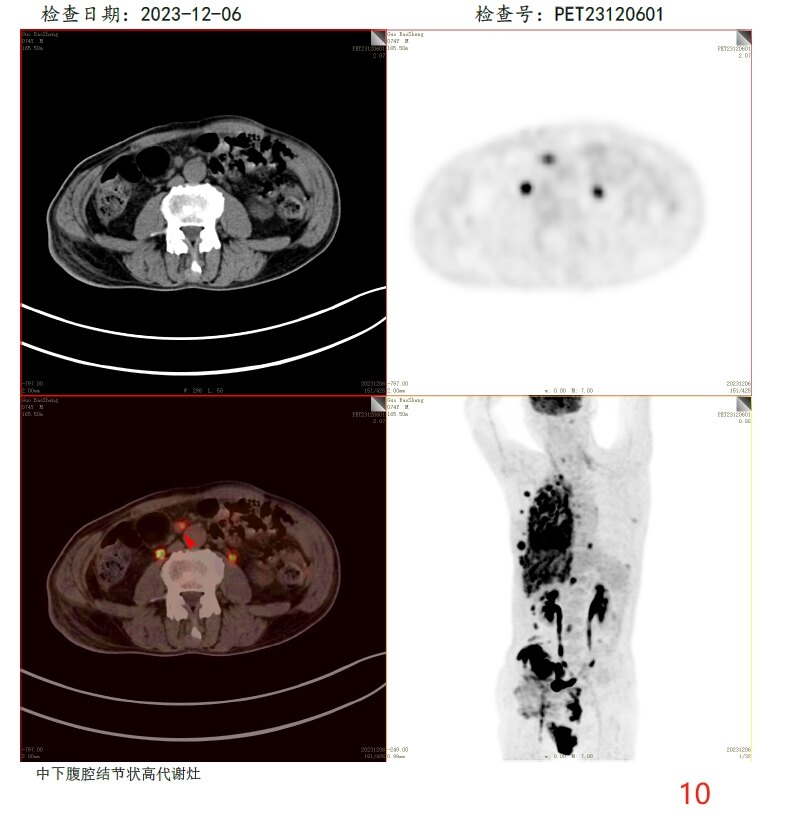

放疗前PET/CT(2023-12-06):

10